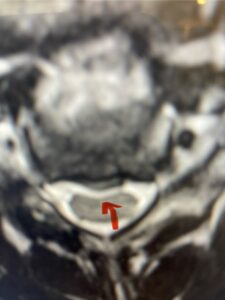

This 61-year-old female with a history of severe osteoporosis and a prior history of a laminectomy from l2-S1 with an L5-S1 instrumented fusion, presents with progressive low back pain and right lower extremity radiculopathy. MRI revealed a grade 1 L2-3 spondylolisthesis with severe stenosis mainly from severe right L2-3 facet joint hypertrophy which was compressing the right L3 descending nerve root. (Fig. 1). She had failed conservative management consisting of physical therapy and pain management with epidurals. She underwent an L1-3 revision laminectomy where we had to dissect a plane underneath the inferior aspect of the L2 lamina. We performed an instrumented fusion at L2-3 with special hydroxyapatite-coated screws to improve fixation to surrounding bone given here severe osteoporosis (Fig. 2) This worked out well and the patient had an uneventful recovery with relief of her leg pain.

Figures 1a: Sagittal and axial T2-weighted lumbar MRIs demonstrating a grade 1 L2-3 spondylolisthesis (red arrow) with severe stenosis secondary to right L2-3 facet hypertrophy (red arrow).